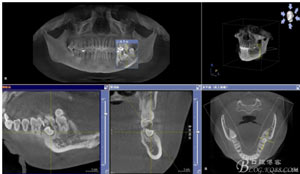

圖1.術(shù)前的CBCT檢查:37頰側(cè)部分牙根被完全壓迫吸收。